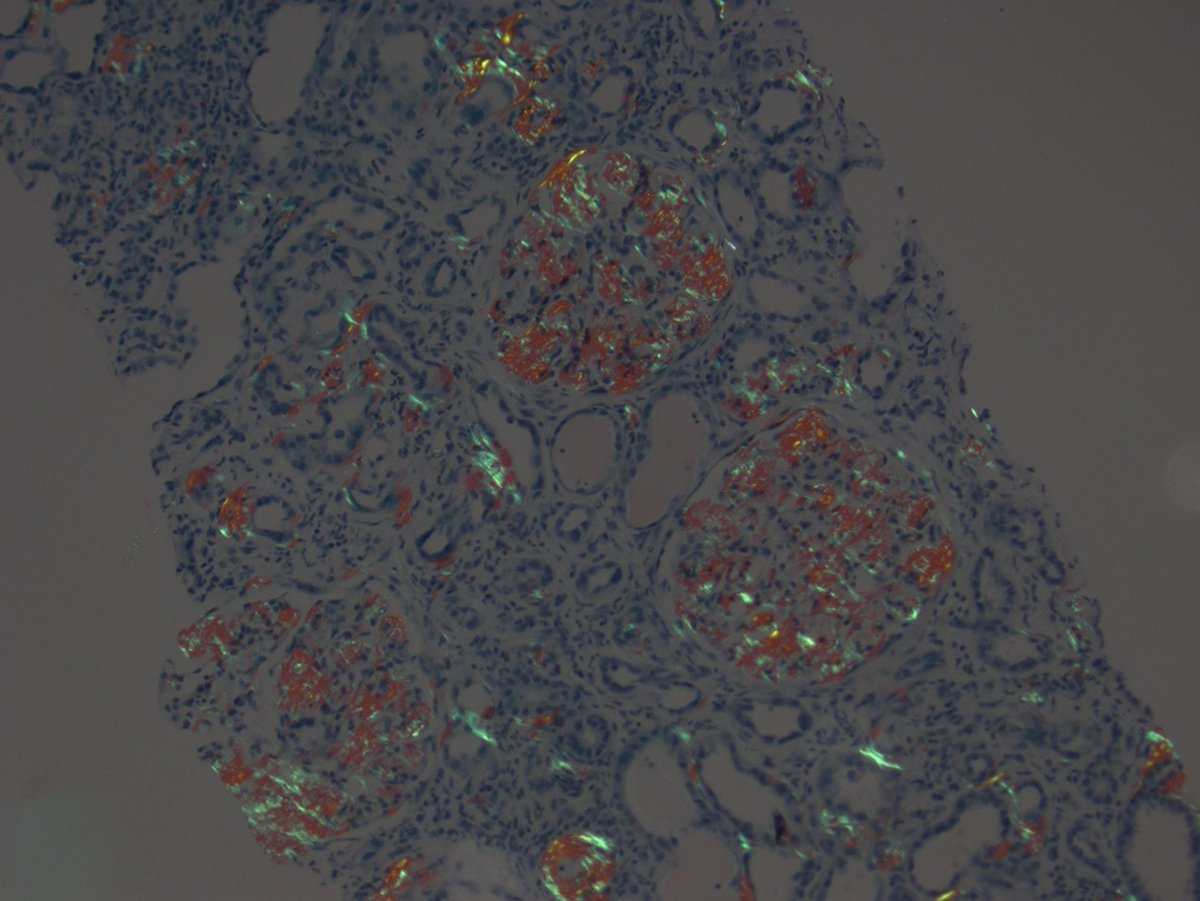

Long weekend often brings urgent cases. Here is one that was STATed, ended up showing anti-GBM GN. Diffuse crescents (nearly 100%). Linear IgG. #RenalPath